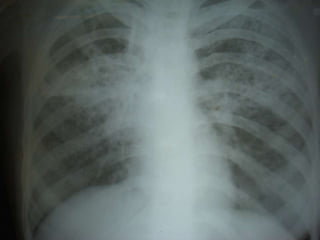

On examination : pt consc,oriented,febrile,pallor,emaciated	              No cyanosis ,no clubbing, no lymphadenopathy,not icteric	              no oral ulcers,no pedal edema, no skin rashes, no external markers of TB  Respiratory examination:	Trachea shifted to rtside,apical impulse normal in position ,	movements of chest wall diminished more in the rt side. B/l coarse creptsCVS:	S1S2 normaly heard ,No murmurAbdomen:	soft, No organomegalyCNS:	No neurological deficit, no meningeal signs

CT Chest: Rt Upper lobe bullous lesion ,Rt middle and lower lobe consolidation with ectatic changes lt upper lobe and lower lobe ECHO: Normal study ,No vegetationsBlood Culture(thrice): Negative for organisms IgM for brucellosis: NegativeTreatment Given: Inj.Cefotaxime,chloroquine,Doxy,Metranidazole,Nebulization, cat-II ATT started

TRC Opinion(30/9/08): 	          Sputum AFB repeat neg; Sputum C/s for TB taken. Even though pt is sputum AFB negative with symptoms of  TB with  increasing infiltrates in CXR advice to con ATT-CatII Even after all these treatment measures pt continued with fever but breathlessness,Cough and expectoration subsided.pt advised to continue cat-II ATT until c&sreport arrives.